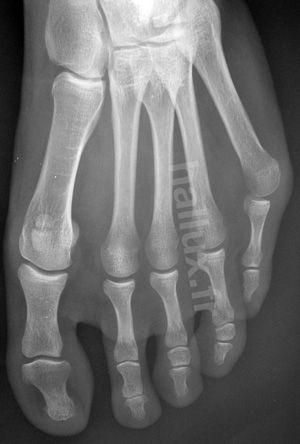

LE SYNDROME DU DEUXIEME RAYON EST SOUVENT LA CONSEQUENCE INELUCTABLE d'un

hallux valgus négligé...

Le patient se plaint de douleurs plantaires (métatarsagies) mais aussi dorsales. L'orteil apparait en griffe et il se produit peu à peu une luxation métatarso-phalangienne dorsale (le deuxième orteil est spontanément relevé par rapport aux autres, voire complètement luxé lorsque se rompt la plaque plantaire, renforcement qui stabilise l'articulation).

Il existe sur le plan clinique, une griffe douloureuse du deuxième orteil, une bursite MP2 et des métatarsalgies

Dans le cadre d'un hallux valgus, il constitue une aggravation des déformations qui peut être un motif de consultation si le patient a négligé les déformations.